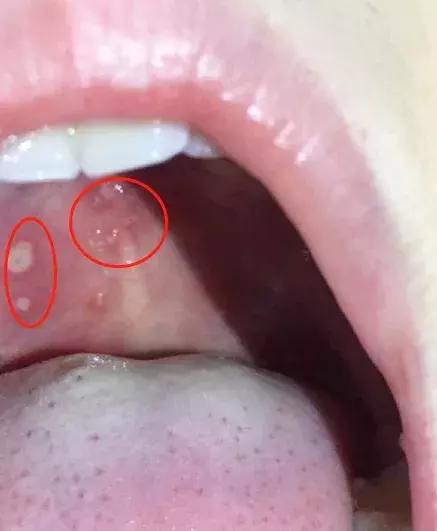

如果宝宝出现低烧不退,小手、小脚、小屁屁和嘴巴里都长出疱疹,那十有八九就是手足口了

像这样

左右滑动 查看详细症状